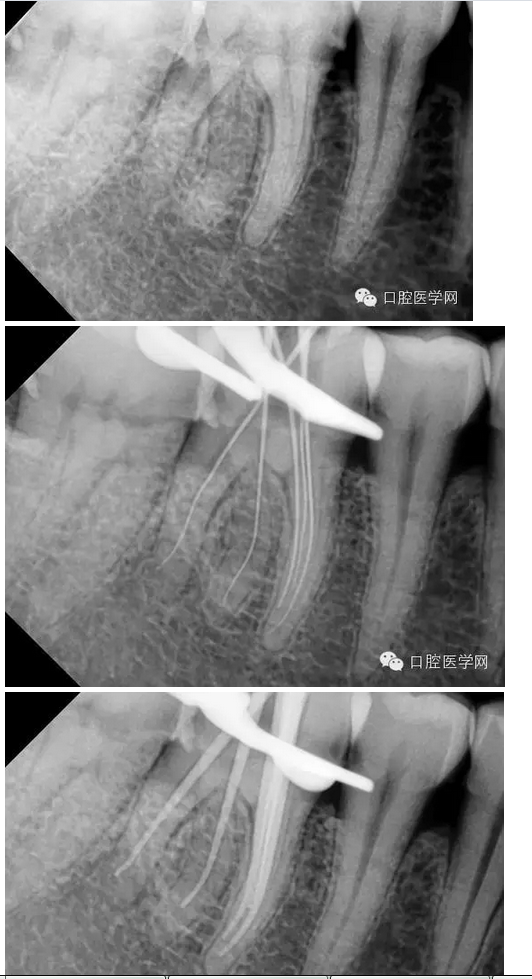

下六五根管治療一例

檢查:#46牙頰側(cè)小洞,探(++),叩(-),冷熱(+++),咬頜正常,牙齦未見不適,未見其它不適。

診斷:#46牙髓炎

治療計(jì)劃:#46根管治療+冠修復(fù)保護(hù)。